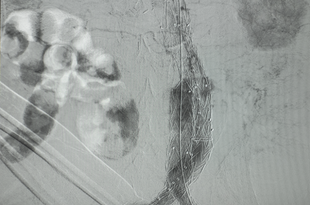

Imaging surveillance is performed after EVAR.

After endovascular aneurysm repair (EVAR), it is necessary to perform and document surveillance imaging – by CT imaging or duplex ultrasound – to monitor patients for graft migration, device failure, or endoleaks. Endoleaks, a persistent flow in the aneurysm sac after EVAR, have been found in >15% of patients more than 5 years after undergoing their procedure. Performing and documenting this surveillance imaging can prevent late rupture and aneurysm-related death.